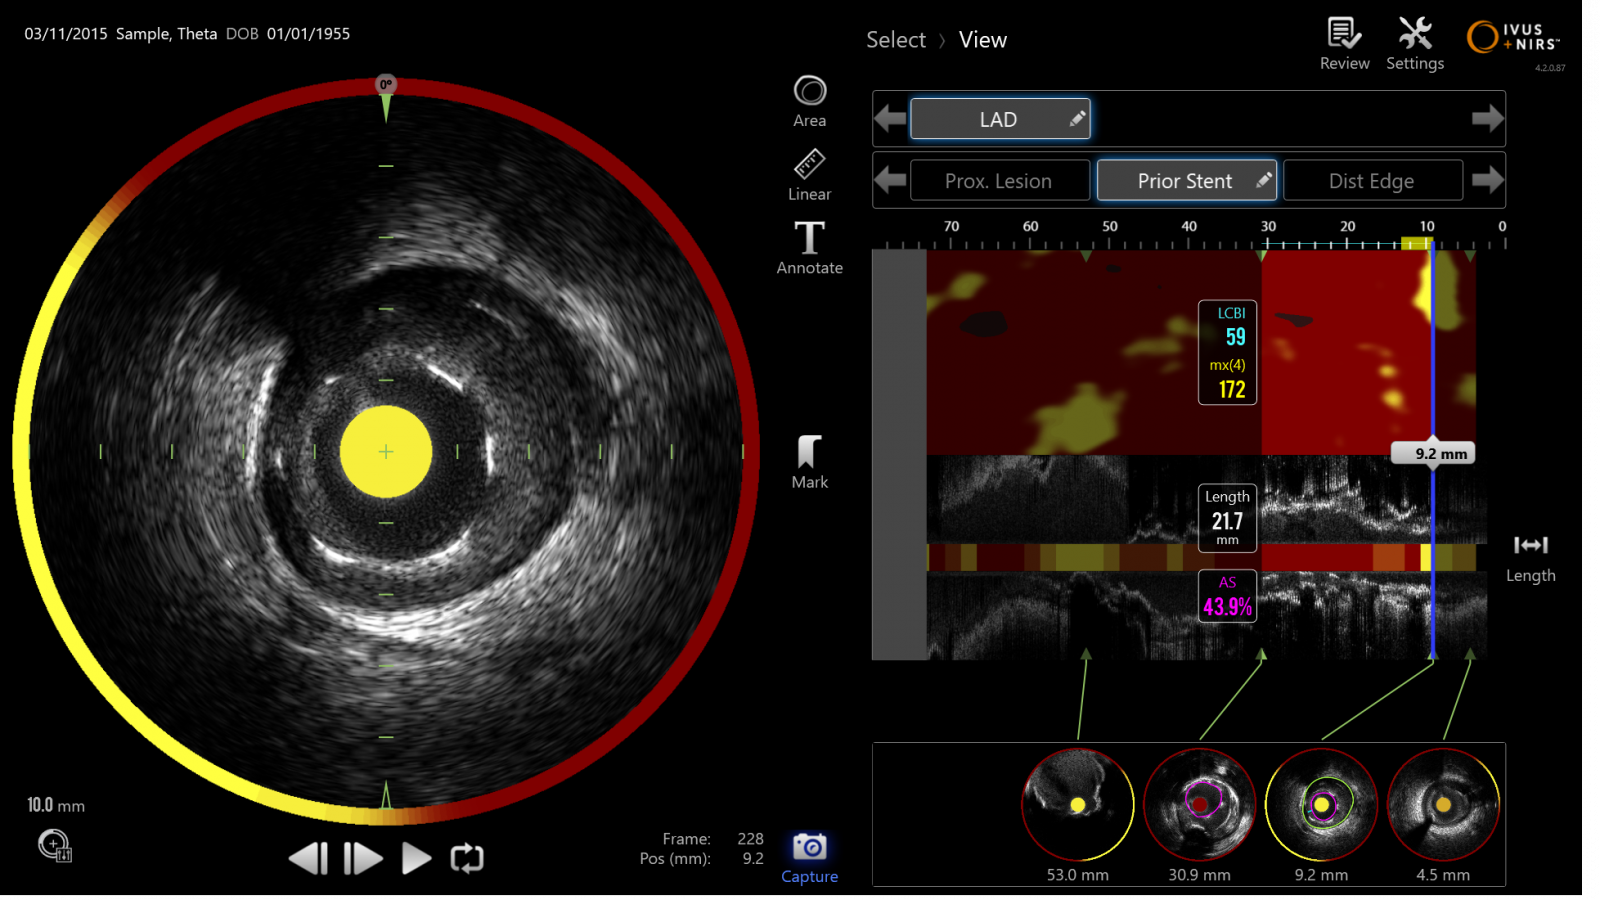

El sistema Makoto™ IVUS + NIRS es una plataforma de imagen intravascular de doble modalidad que combina ultrasonido (IVUS) de alta definición con espectroscopía infrarroja cercana (NIRS), permitiendo evaluar simultáneamente la anatomía del vaso y la composición de la placa aterosclerótica durante intervenciones coronarias.

Integra dos tecnologías complementarias en un solo procedimiento:

IVUS: Visualiza la estructura del vaso, diámetro, lumen y morfología

NIRS: Identifica placas ricas en lípidos y su distribución

Caracterización completa de la lesión en tiempo real, mejorando la toma de decisiones clínicas durante el PCI.

Evaluación simultánea de estructura y composición

Permite entender no solo el vaso, sino el tipo de placa

Detección de placas vulnerables (lipídicas)

Ayuda a identificar lesiones con mayor riesgo de eventos

Optimización del procedimiento PCI

Mejora la selección de estrategia y resultados